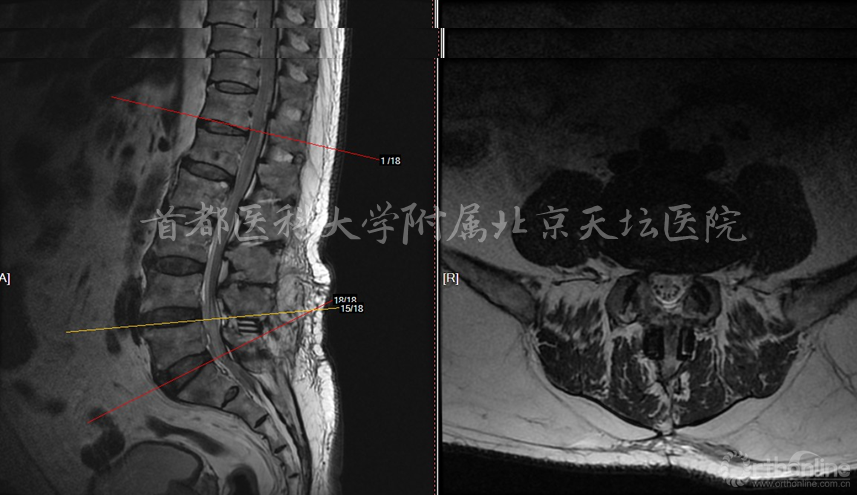

影像资料: